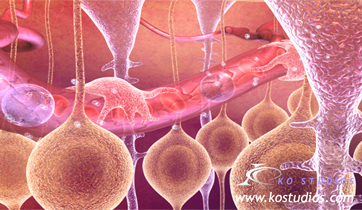

Diastolic Cardiac Insufficiency

Sanofi

ScienceProd, Paris

The Angiotensin - Aldosterone - Renin system is triggered by the thickening of the left ventricle and improper filling of the venticular chamber. This triggers the release of aldosterone, noradrenaline, and angiotensin II which binds to fibroblasts, releasing collagen and increasing myofibril rigidity.